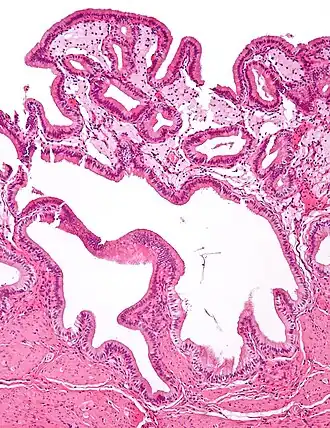

In surgical pathology, strawberry gallbladder, more formally cholesterolosis of the gallbladder and gallbladder cholesterolosis, is a change in the gallbladder wall due to excess cholesterol.[1]

Micrograph of cholesterolosis of the gallbladder -

Micrograph of cholesterolosis of the gallbladder